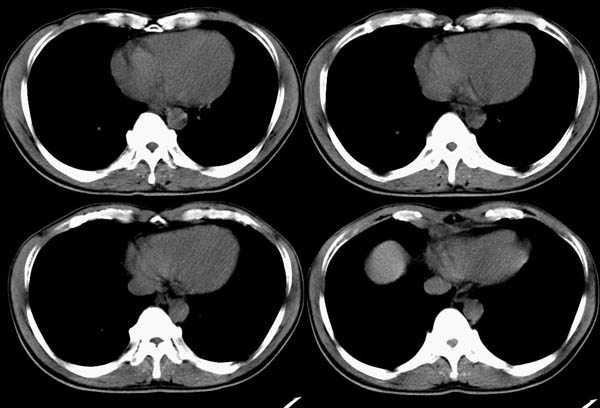

m50y以腹疼、腹胀2小时就诊。腹透肠胀气较明显,余无明显异常。做ct时腹疼已明显缓解;病人否认外伤史,否认血液病变、否认肝炎史。建议第二天做ct增强,病人第二天放弃了增强。脾脏区较高密度影ct值为60hu,正常脾脏ct值为45hu(窗宽:150,窗位:56)。

脾区病变局部2mm重建: